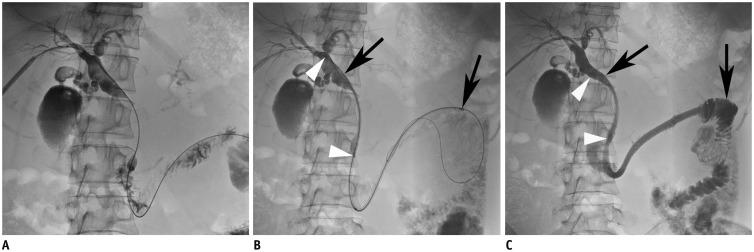

This prospective study enrolled 48 consecutive patients (31 men, 17 women; mean age, 61 years; age range, 31-77 years) with malignant extrahepatic biliary obstructions from May 2013 to December 2015. All patients were treated with a double-stent system with long duodenal covered extension (16 cm or 21 cm).

The stents were successfully placed in all 48 patients. There were five (10.4%) procedure-related complications. Minor complications were self-limiting hemobilia (n = 2). Major complications included acute pancreatitis (n = 1) and acute cholecystitis (n = 2). Successful internal drainage was achieved in 42 (87.5%) patients. Median patient survival and stent patency times were 92 days (95% confidence interval [CI], 61-123 days) and 83 days (95% CI, 46-120 days), respectively. Ten (23.8%) of the 42 patients presented with stent occlusion due to food impaction with biliary sludge, and required repeat intervention. Stent occlusion was more frequent in metastatic gastric cancer patients with pervious gastrectomy, but did not reach statistical significance ( = 0.069).

Percutaneous placement of a double-stent system with long duodenal extension is feasible and safe. However, this stent system does not completely prevent stent occlusion caused by food reflux.